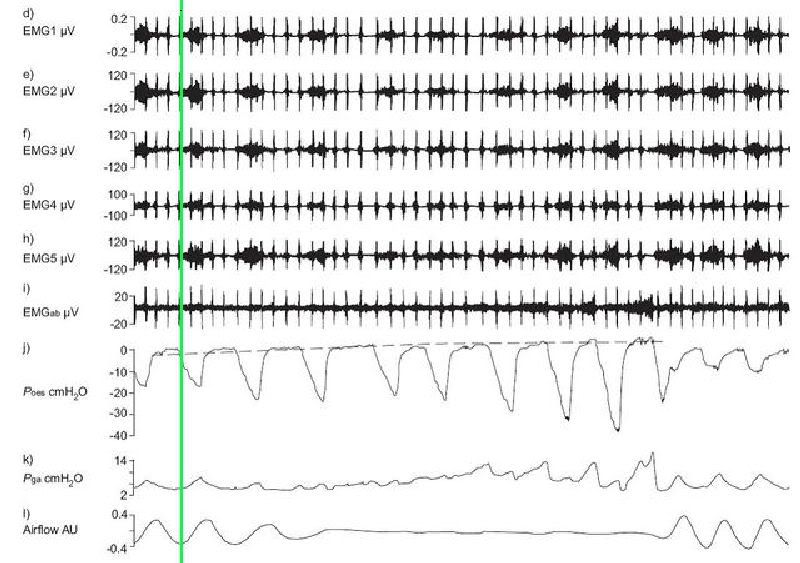

As I stated in the other thread, this patient was demonstrating increased respiratory drive as the patient was cycling through respiratory events. There was both an increase in inspiratory drive(increased genioglossus muscle activity) and expiratory drive (gastric pressure [Pga] swings during expiration). During "normal breathing", swings in Pes and Pga are opposite i.e. as Pes goes down during inspiration, Pga goes up. However, during increased expiratory drive (see figure below), contraction of the abdominal muscles during expiration increases Pga. The vertical line clearly shows that peak Pga occurs during expiration i.e. cranking up abdominal muscles. Furthermore, peak Pes appears to to increase with rising expiratory Pga swings. See breath designated by a *. As you can also see by the flow trace, it appears that expiration is also obstructed. (This patient had normal lung function). I believe that the increase in peak Pes is simply due to contraction of the abdominal muscles increasing airway pressure. I think it's also important to distinguish peak expiratory Pes versus end-expiratory Pes. End-expiratory Pes in the example below is predominantly <10cmH20.Muffy wrote:I'm trying to understand why the "20 cmH2O patient" had such a high PES in the absence of CPAP and/or abdominal compression. It would seem to be from either an error in the calibration of PES transducer to NPSG or another factor present (like the guy had PEPI compression plus 3 Pizza Hut "Belly Busters" on the way into the sleep lab.

Sure thing. The picture below shows a 60 sec segment which includes that breath indicated by a *. You will have to excuse what I said last night as it was very late. So expiration wasn't "completely" obstructed but can you please make a comment about his expiratory flow profile? I'm certainly no expert in spirometric procedures, but his expiration is of interest. During times of increased drive, he tended to get a brief period of increased flow (generally in the first second), before tapering off to lower flow rates for the rest of expiration. Again, look at the * breath. What's going on here? The expiratory Pga swing is massive, with peak Pga of ~28cmH20. Peak Pes for this expiration is ~20cmH20. However, end-expiratory Pes is ~5cmH20. Is this patient experiencing a lot of iPEEP?Muffy wrote:Actually, I don't see anything in the flow trace to indicate that expiration is obstructed. If anything, it shows quite the opposite.split_city wrote:See breath designated by a *. As you can also see by the flow trace, it appears that expiration is also obstructed.

Muffy

This patient had normal lung function with FEV1 and FVC both >80% predicted. He wasn't a smoker and not overly obese, with a BMI of ~33 (I think). However, this patient was a little odd compared to the rest of the patients in the group. There were certainly patients displaying expiratory swings in Pga but only during an apnea, and generally only towards the end of the apnea. This guy was showing these expiratory Pga swings (quite large ones at that) for a fair % of the night. I kept thinking maybe the Pes catheter was too low or even in the stomach. But he always showed the typical pressure swings i.e. Pga goes up while Pes went down during inspiration, during stable breathing. This certainly doesn't discount the possibility that the dipahragm moved up, resulting in the Pes catheter being below the diaphragm during unstable breathing.

I imagine you're calling end-expiratory Pes at the red line, but assuming your signals are synched, I think it would be more appropriately called at the green lines:

This would better coincide with the GN EMG, end of abdominal effort and VT. I think the baseline Pes is 20 cmH2O also because the tops remain flat even when expiratory flow significantly slows, both in some of the much less aggressive individual breaths and the inherent nature of the latter part of each breath. BTW, did you have inductance plethysmography belts on, and can you find a central apnea or some slow breathing where the breaths don't run into each other somewhere?

Nope, I wouldn't say that red line is where the breath starts. Here's where I think those three breath you identified start. I have also added mask pressure, epiglottic pressure (not the best trace as the catheter is slightly blocked) and a single diaphragm EMG channel. IMO, end-expiratory Pes is still below 10cmH20, and not the peak as you are suggesting.Muffy wrote:I imagine you're calling end-expiratory Pes at the red line, but assuming your signals are synched, I think it would be more appropriately called at the green lines: